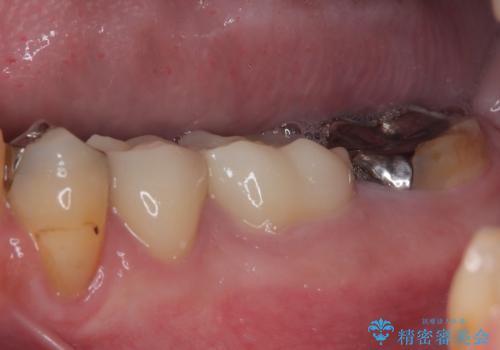

大臼歯の治療後に海外赴任され、数年ぶりに帰国されました。

奥歯に痛みがあるとのことで診察を行ったところ、海外(アメリカ)にて処置をした手前の歯が既に失活していることが分かりました。なお、治療を行った大臼歯はレントゲン写真上の治癒が認められました。

症状のあった歯に対しても根管治療を行い、同様に補綴治療を行いました。